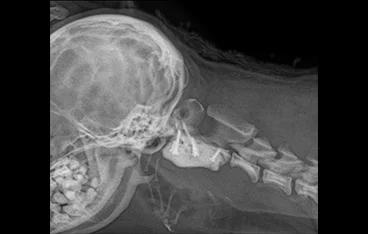

후두골이형성증 (COMS)

FMD

• 후두골이형성증